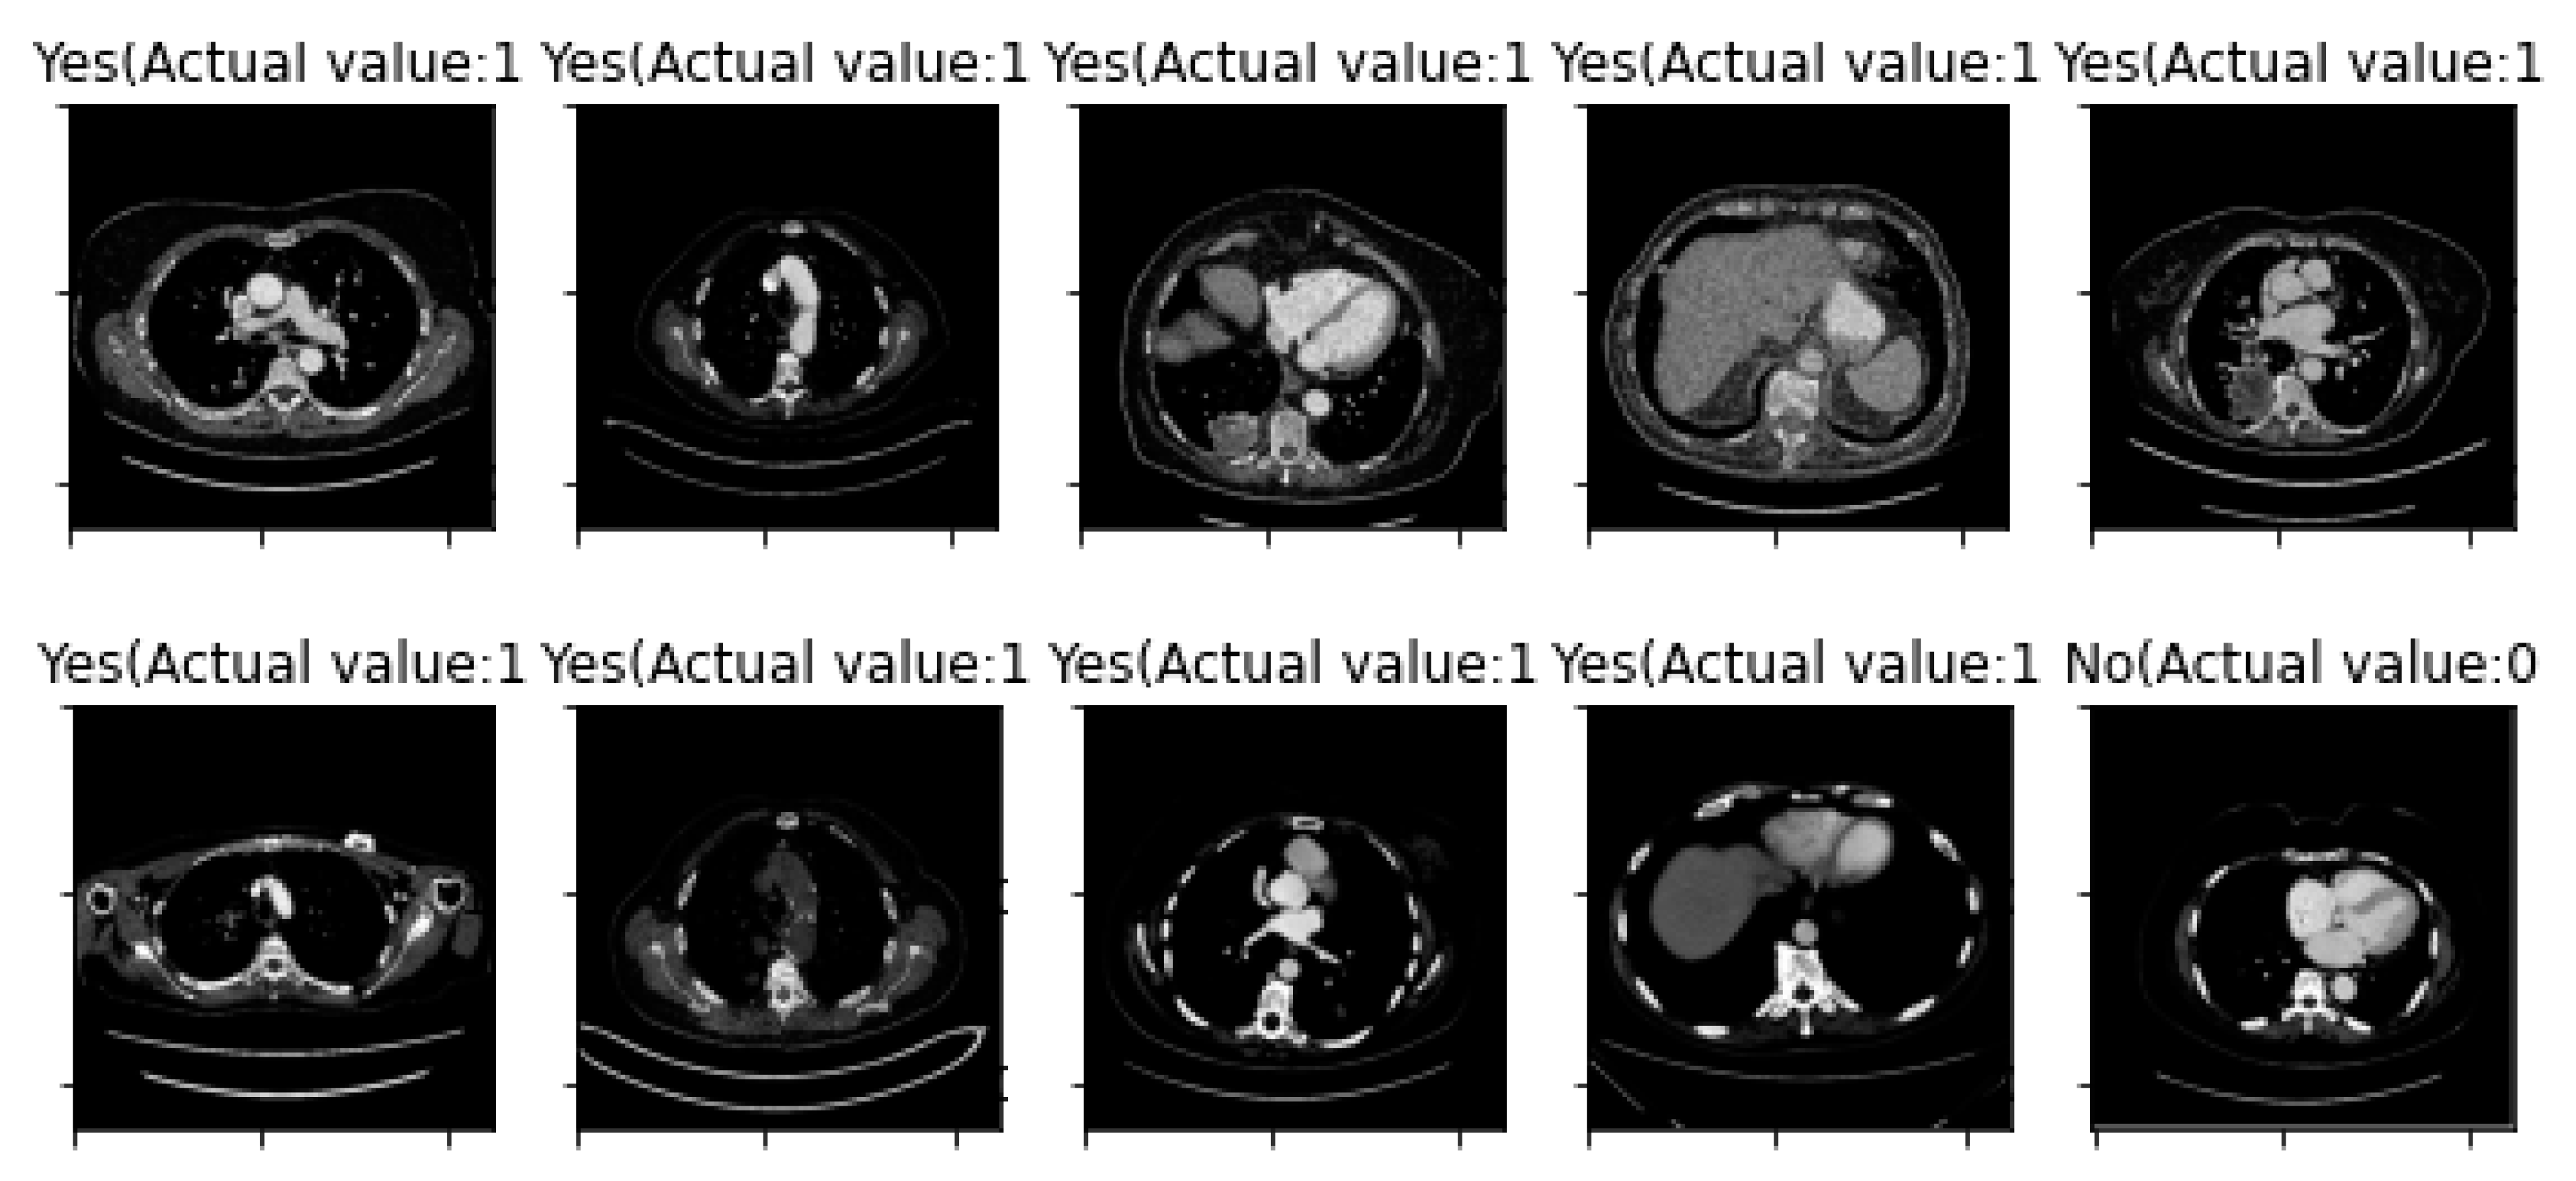

| Image Number | Overlaid Image | Deep Lesion Label | CNN Result | Clinical Radiologist’s Diagnosis | Grad-CAM Helpfulness |

|---|---|---|---|---|---|

| 1 | ![]() | Has Tumor | Has Tumor | Has Tumor | Some |

| 2 | ![]() | Has Tumor | Has Tumor | Has Tumor | Yes |

| 3 | ![]() | Has Tumor | Has Tumor | Has Tumor | Yes |

| 4 | ![]() | Has Tumor | Has Tumor | Has Tumor | Yes |

| 5 | ![]() | Has Tumor | Has Tumor | Has Tumor | Yes |

| 6 | ![]() | No Tumor | Has Tumor | Has Tumor | Yes |

| 7 | ![]() | Has Tumor | Has Tumor | Has Tumor | Yes |

| 8 | ![]() | Has Tumor | Has Tumor | Has Tumor | Yes |

| 9 | ![]() | Has Tumor | Has Tumor | Has Tumor | Some |

| 10 | ![]() | Has Tumor | Has Tumor | Has Tumor | Yes |

| 11 | ![]() | Has Tumor | Has Tumor | No Tumor (Cyst) | Some |

| 12 | ![]() | Has Tumor | Has Tumor | Has Tumor | Yes |

| 13 | ![]() | Has Tumor | Has Tumor | No Tumor | Yes |

| 14 | ![]() | Has Tumor | Has Tumor | No Tumor (Inflammation of the Biliary Tract) | Some |

| 15 | ![]() | No Tumor | Has Tumor | No Tumor (Cyst) | Some |

| 16 | ![]() | Has Tumor | Has Tumor | Has Tumor | Yes |